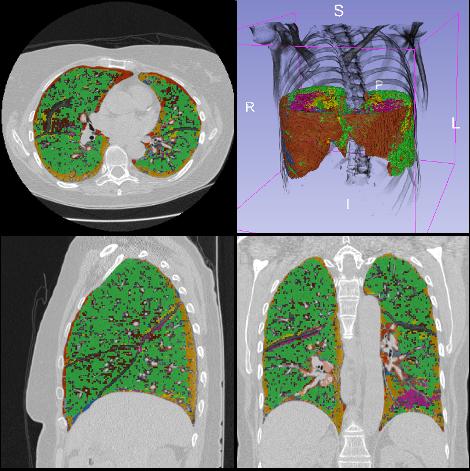

Diferentes tipos de tejido pulmonar que anticipan la aparición de la enfermedad intersticial pulmonar a partir de un TAC de una persona fumadora. (Foto: UPM/CIBER-BBN)

“En este trabajo aportamos el primer método basado en deep learning para identificar y clasificar patrones radiográficos de enfermedad pulmonar intersticial en etapas tempranas en imágenes de tomografía computarizadas, considerando ocho clases radiográficas de tejido pulmonar”, explica María Jesús Ledesma, investigadora del CIBER-BBN y última firmante del trabajo.

Para entrenar y probar el sistema, los investigadores utilizaron un total de 37.424 muestras de tejido radiográfico correspondientes a ocho clases distintas de características del tejido pulmonar de 208 tomografías computarizadas. Según subrayan los investigadores, “son necesarios nuevos diseños e investigaciones “que permitan abordar la identificación de estos cambios precoces en el parénquima pulmonar”. Los datos que se han usado en este estudio provienen del estudio COPDGene.